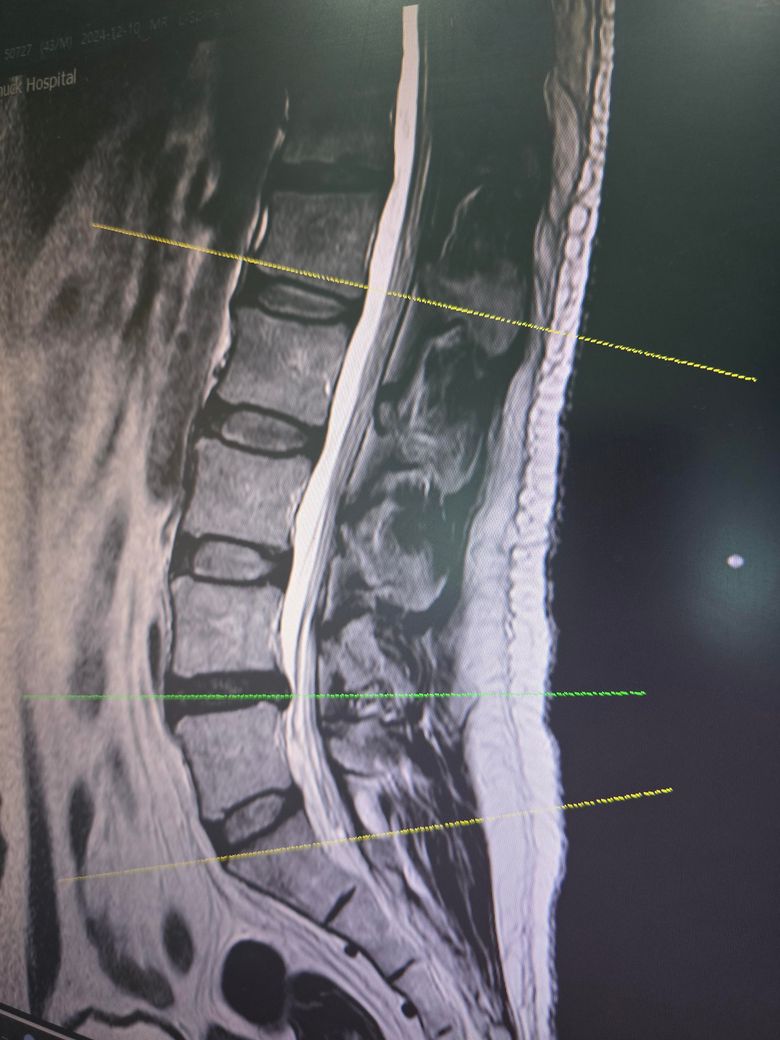

요추4,5 디스크 판정인데 수술을 권유하시는데 그정도로 안좋은 상태일까요?

금일 mri 촬영했는데 시술이나 보존치료가 아닌 단방향내시경수술을 권하시네요

시술단계가 아닌 수술이라는데 그정도일까요?

• 3번 째 사진